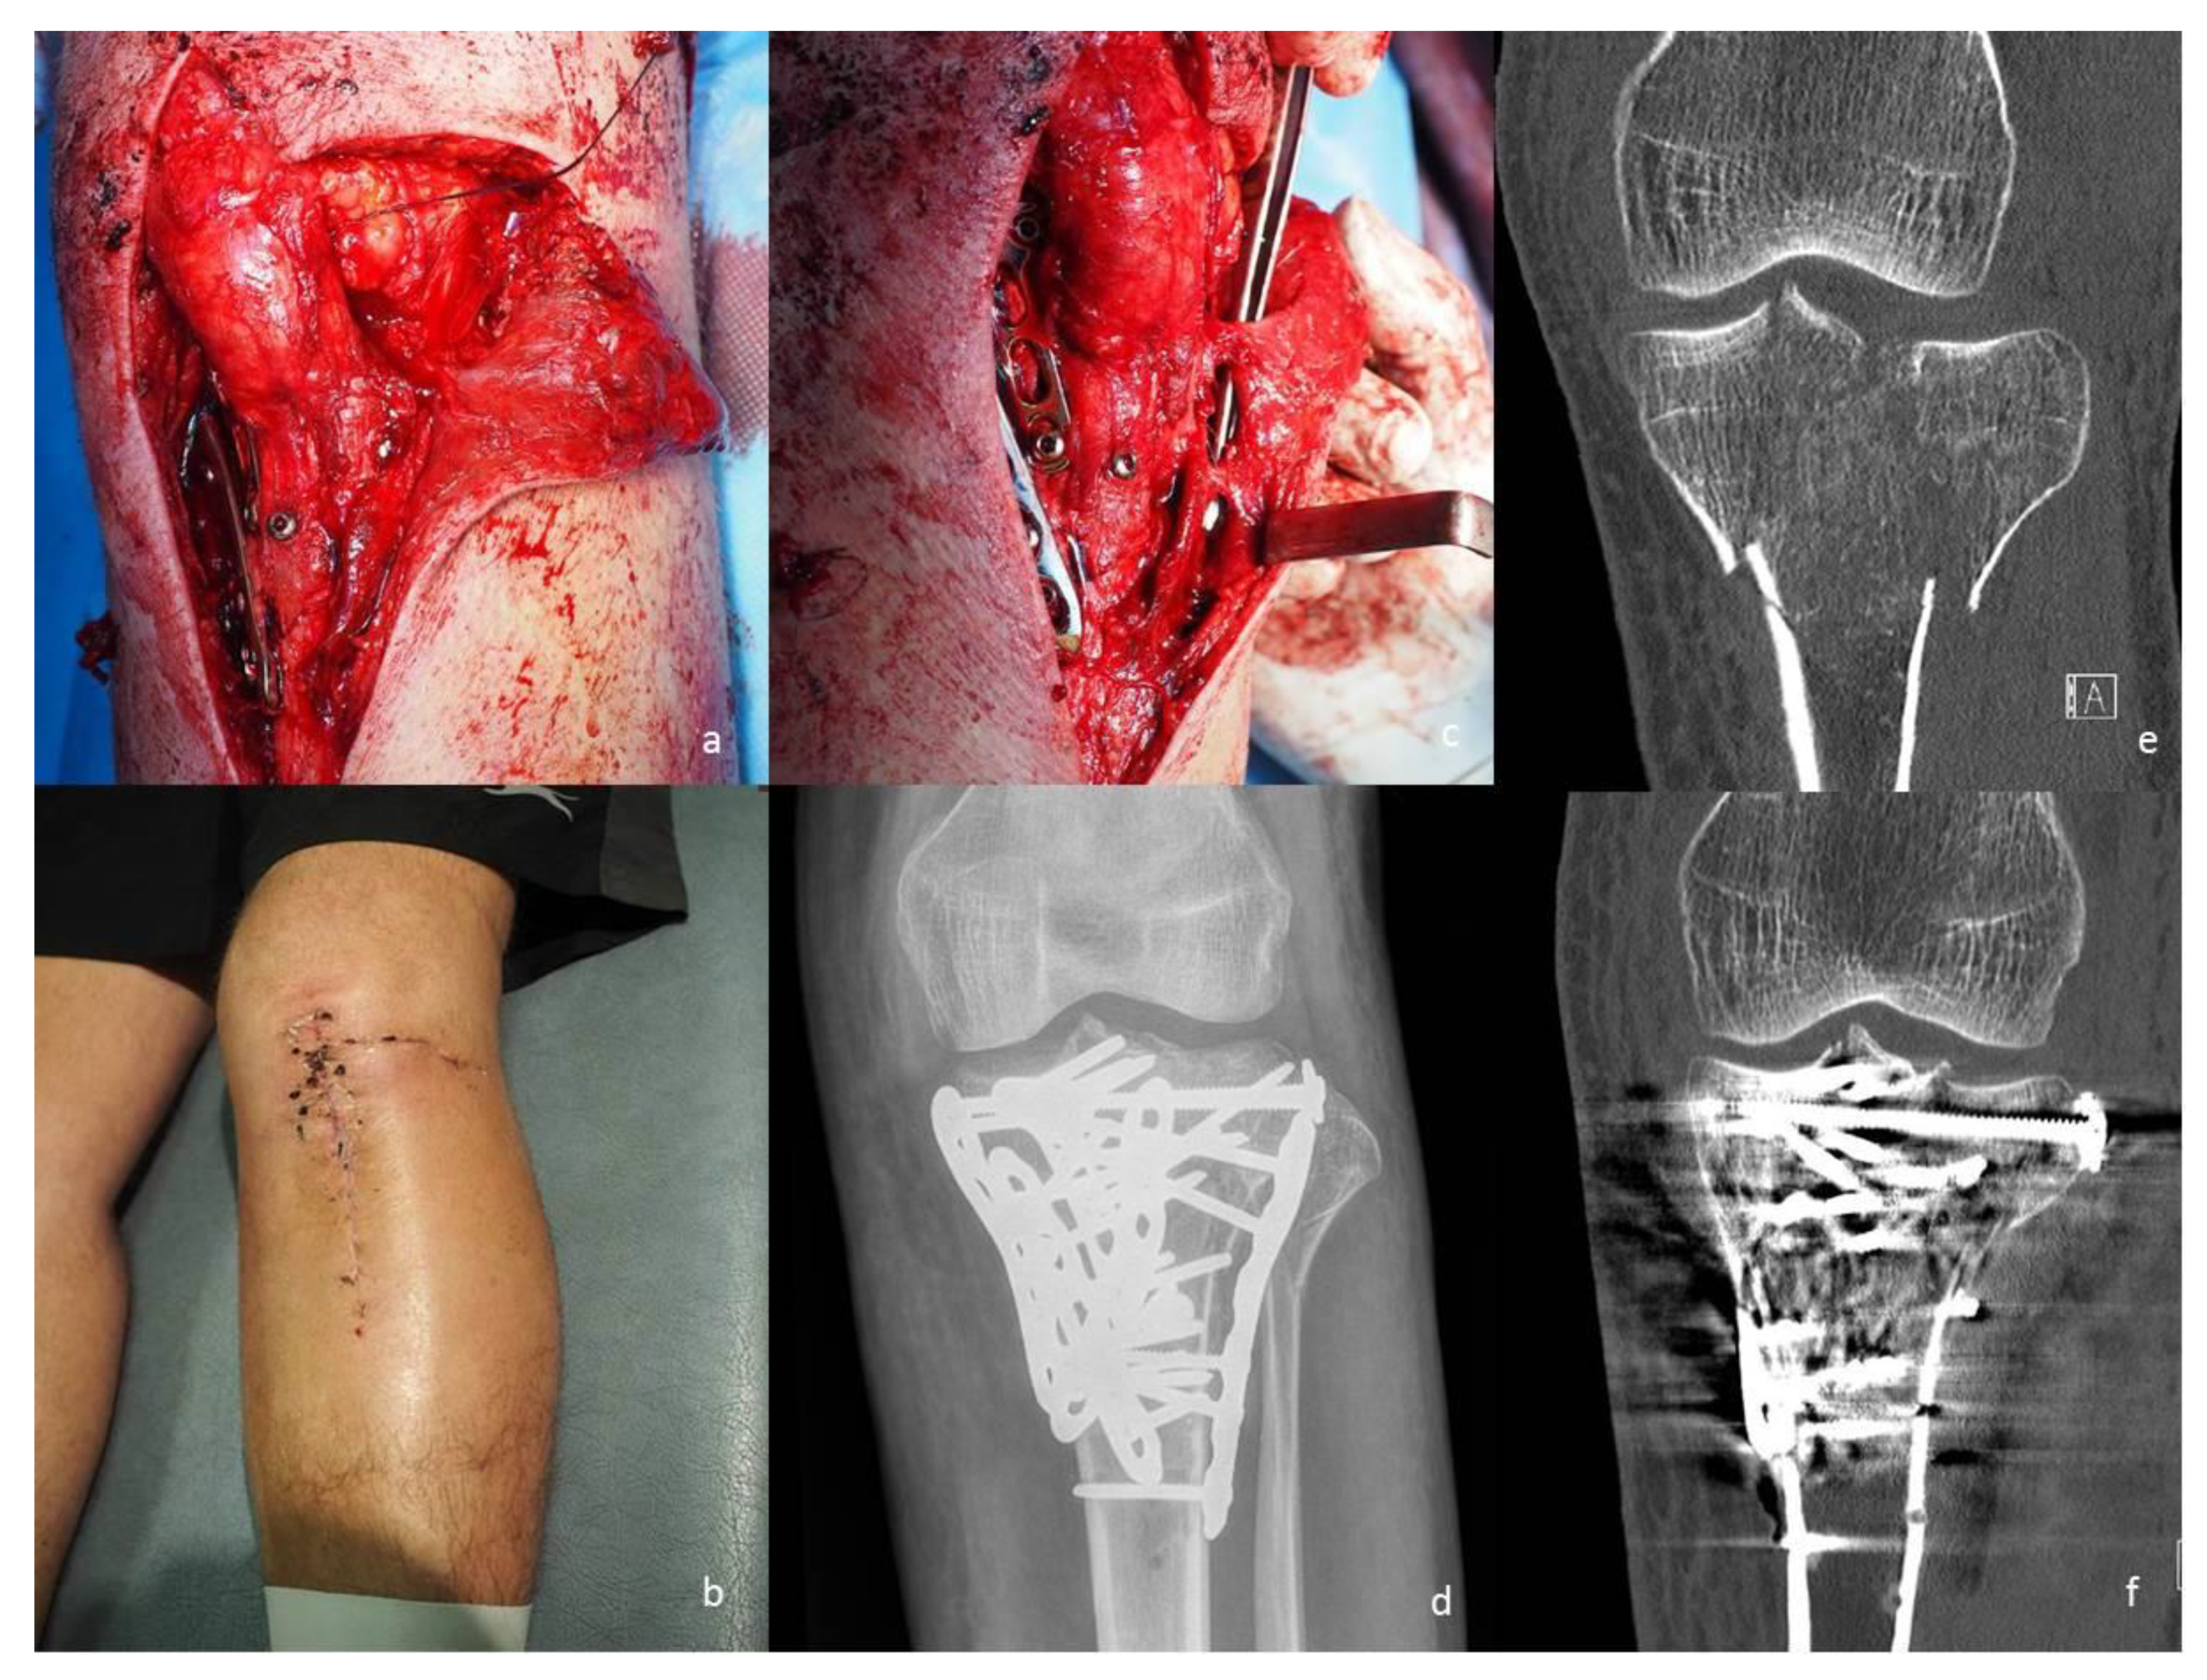

2.1. Angiosome- or Perforator-Sparing Surgical Technique